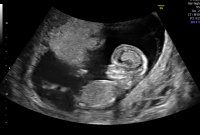

En liten gutt koser seg og vokser inni magen min.Vi fikk til og med se den lille hikke. Han klarte ikke ligge i ro et sekund, så godt å se at han er aktiv, sprellet med beina og vinket til oss! :D Ingen tegn til noe avvik eller kromosomfeil, så fantastisk godt å høre at lille ser frisk ut. CRL 9 cm :Heartblue sjekk siste bilde, der ser man rumpa og den lille saken som stikker ut:joyful: